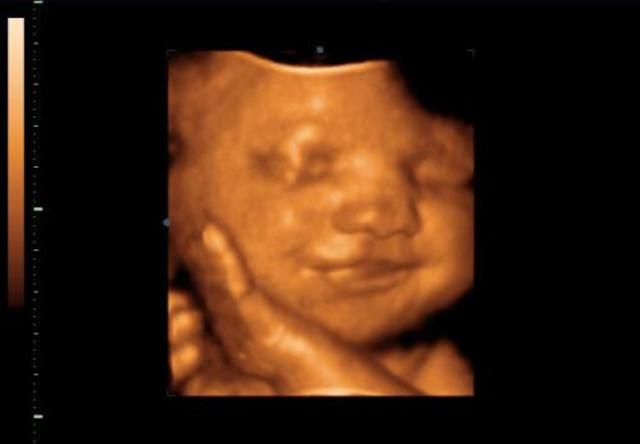

A huszadik héten a baba fejének az átmérője már 47 mm, a testtömege körülbelül 30 dkg, közben a magzat hallása is egyre élesebbé válik.